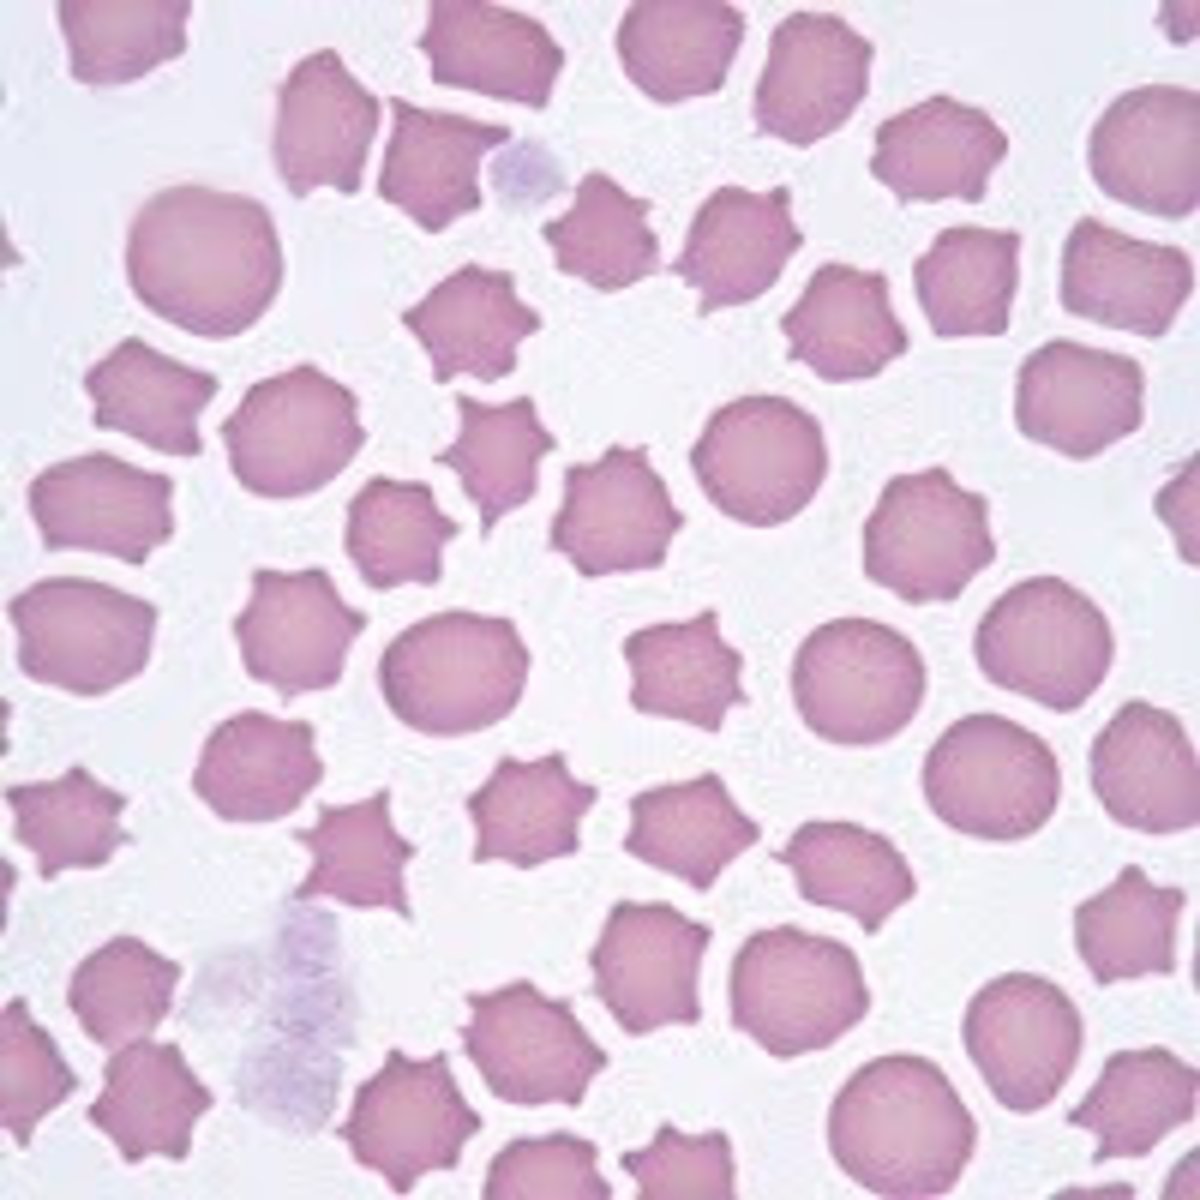

crenation

UNIFORM, evenly spaced, short projections around the RBC's

mainly caused by artifact "old" blood

- too much anticoagulant to blood ratio